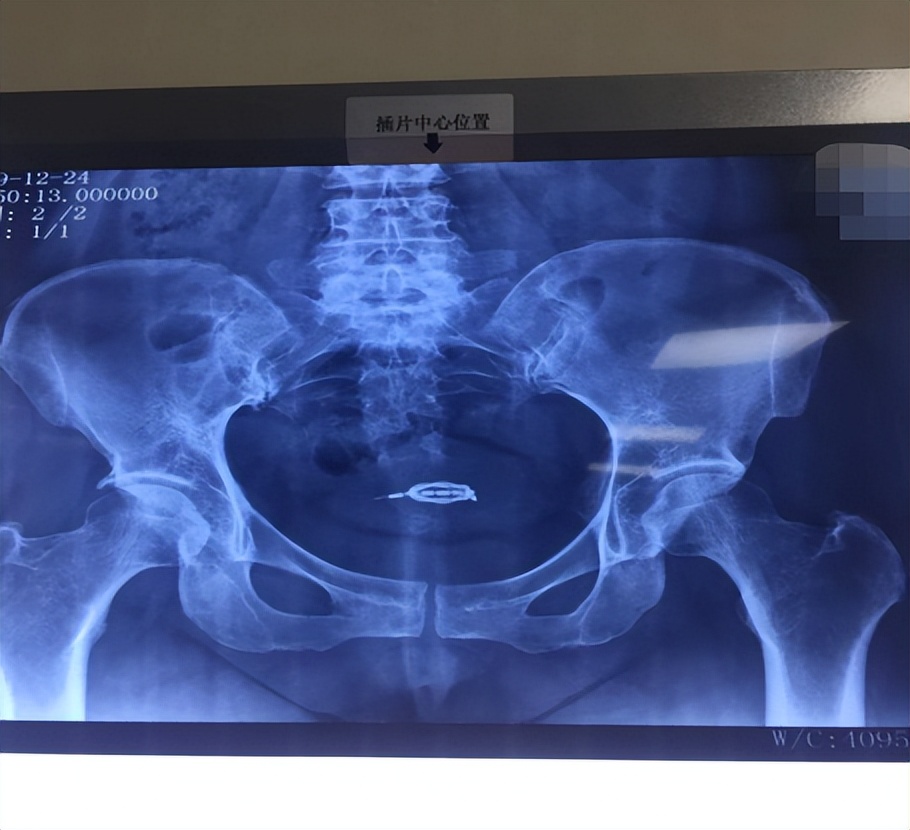

54岁的金阿姨,已经半年没有来过月经了,认为自己已经绝经了,想要把戴了29年的节育器取出来,于是来到医院进行了一系列的取环术前检查,各项检查均正常,取环过程很顺利。

取出一个完整的“O”环,金阿姨想这个心里的大石头可是落了地,没想到的是,金阿姨回家以后阴道流血10余天不干净。

于是金阿姨又在当地的医院查X线,检查结果提示:宫内竟然还有节育器!

这是怎么回事?

△X线提示宫内有节育器